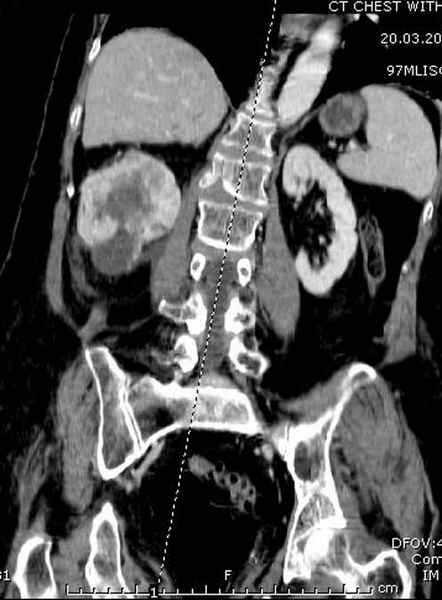

Со слов, больная ничем не болела, только последние 3 месяцев чувствовала боли в бедренной области. КТ брюшной полости подтвердил увеличенную правую почку. (5-6)

Для предупреждения кровотечения во время рассверливания, за день до операции провели эмболизацию сосудов питающий метастаз. http://radiology.rsnajnls.org/cgi/reprint/150/3/673.pdf (7-11, 12-15-16)